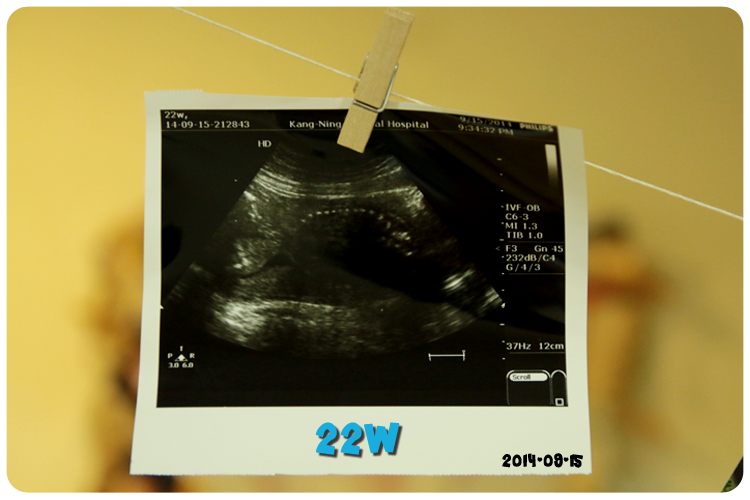

黃色箭頭是寶寶的頭,藍色箭頭是寶寶的屁股,中間白色點點連成的線就是寶寶的脊椎嘍!

至於超音波照片右邊的英文跟數字醫生一直都沒有特別解釋,

是之前看了Babyhome的文章才知道那些密碼代表著什麼,

不過發現...我寶寶的超音波上的密碼完全沒有一樣的,下次產檢一定要問問醫生到底代表什麼意思~